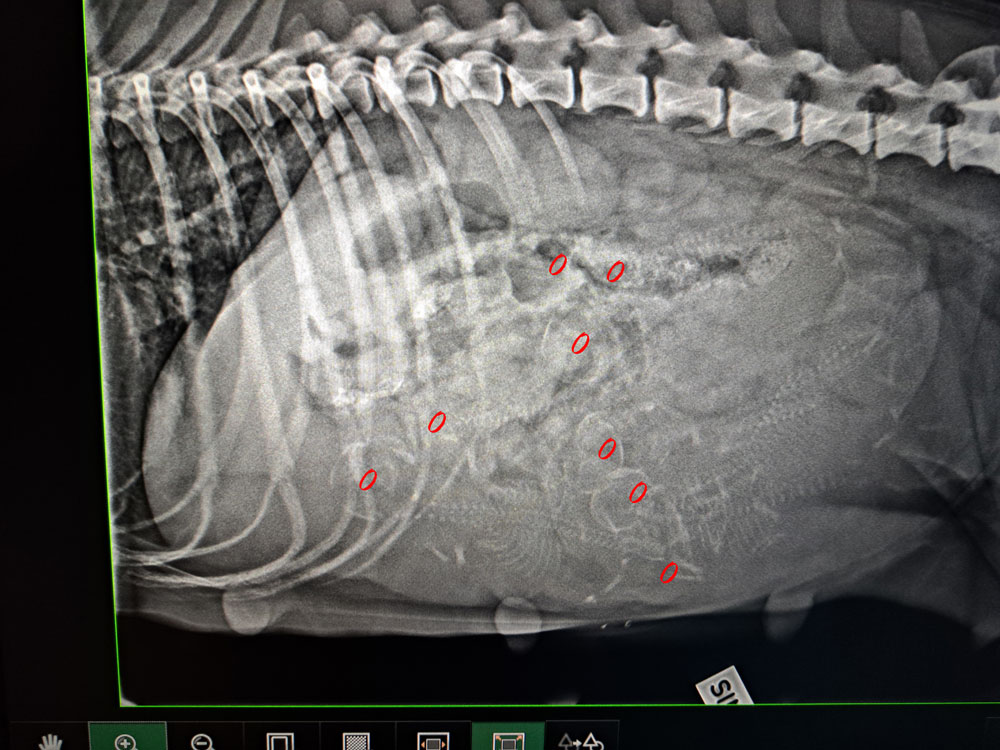

Har palperat Delli idag och hon är dräktig!

I have palpated Delli today and she is pregnant!